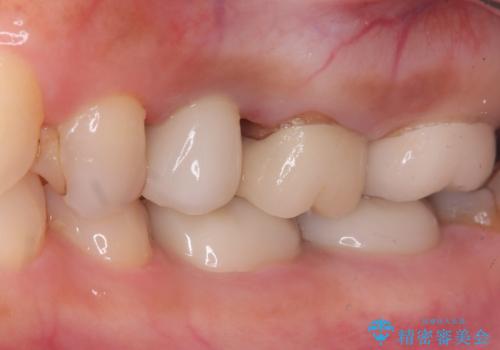

左上第一小臼歯のインプラント治療

- 患者様は、左上第一小臼歯の垂直性歯根破折が確認され、抜歯が必要となりました。本来、抜歯即時埋入を適用できるケースでしたが、患者様のご都合によりブリッジとインプラントで一度悩まれるとのことで待時埋入となりました。治療計画では、上顎の骨の状態を慎重に評価し、デンサーバーを用いてドリリングを行うことで、上顎洞粘膜を傷つけずにインプラントを埋入する方法を選択しました。埋入後の安定を確保するため、術後の経過観察を慎重に行います。

待時埋入では、抜歯後に骨の再生を待つ必要があり、即時埋入に比べて治療期間が長くなります。しかし、デンサーバーを使用した精密なドリリングによって、上顎洞粘膜を破らずにインプラントを埋入することができ、術後の合併症リスクを最小限に抑えることができました。インプラント埋入後は、骨との結合を待ちながらしっかりとしたケアと定期的な検診を行い、最終的な補綴物の装着に備えます。